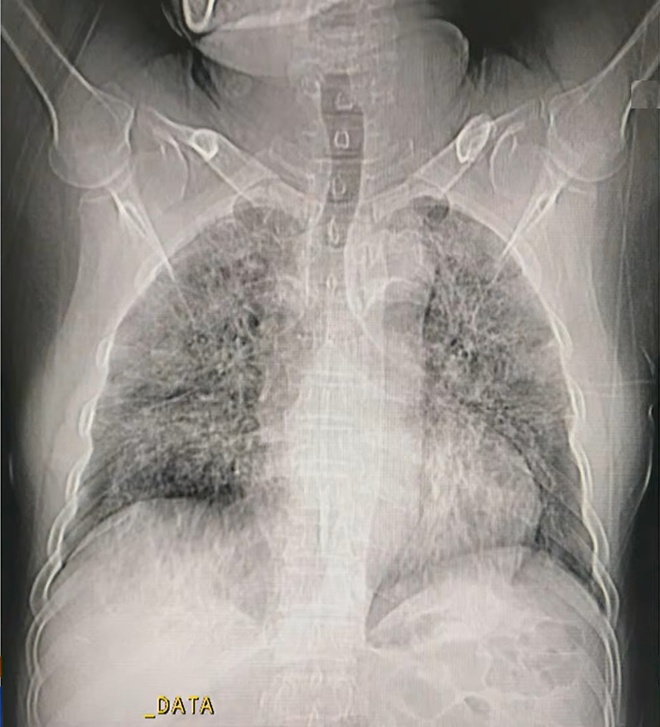

Hình ảnh phổi của ca mắc Covid-19 thứ 867, các tổn thương cho thấy người này ở giai đoạn đỉnh bệnh. Ảnh: Bệnh viện Đại học Y Hà Nội.

Ở giai đoạn đỉnh bệnh (sau 10-13 ngày), phổi của người mắc Covid-19 xuất hiện các vùng đông đặc. Đây cũng là thời điểm cơ quan này bị tổn thương nhiều nhất.